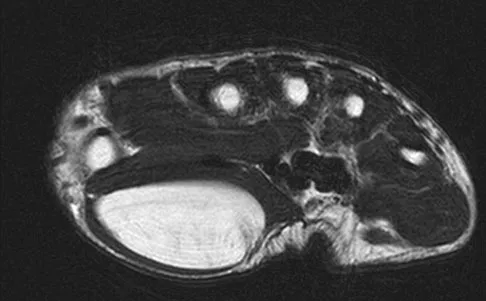

A 35-year-old woman who runs long distance has had posterior calf tenderness for the past 3 months. A clinical photograph is shown in Figure 10a, and MRI scans are shown in Figures 10b and 10c. Management at this point should consist of